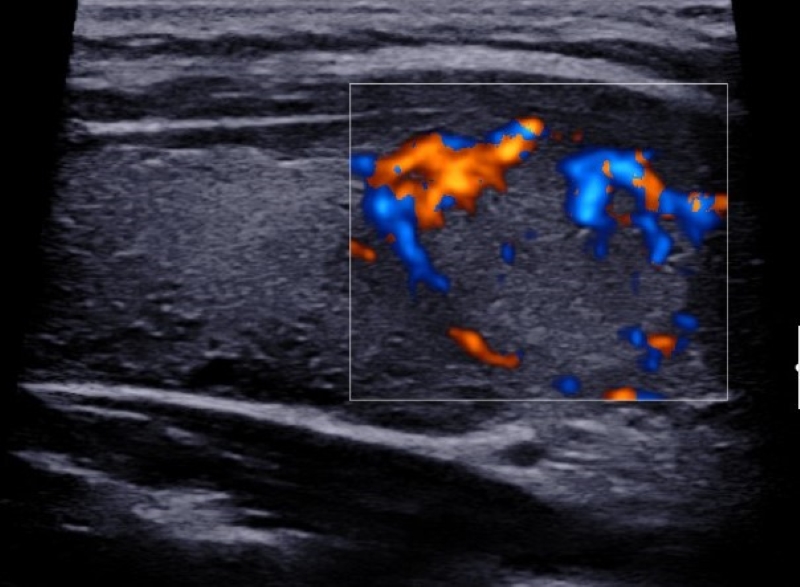

Vascularización

La vascularización se evalúa con la herramienta de Doppler color, y se debe determinar si esta se encuentra ausente (Fig. 18) o aumentada en el nódulo en relación con el parénquima tiroideo. La vascularización aumentada puede presentar dos patrones: central (Fig. 19) y periférico (Fig. 20), siendo el aumento de la vascularización central con disposición caótica la que presenta mayor riesgo de malignidad2,14,19,22,23,24. Un patrón vascular periférico se asocia mayormente con benignidad15,18, aunque algunos autores han calificado a la vascularización como una característica no significativa para diferenciar nódulos benignos de malignos2,3,14,16.